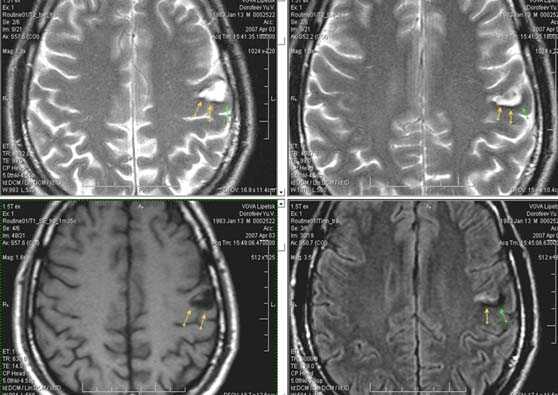

Характерным проявлением ДЭП на МР-томограммах является наличие множественных очагов глиоза.

В белом веществе левой лобной и обеих теменных долей, преимущественно субкортикально, выявлены множественные мелкие очаги хронической ишемии (большинство локализованных в бассейне правой средней мозговой артерии).

Проявлением хронической ишемии является также развитие выраженных дистрофических изменений белого вещества паравентрикулярной локализации - лейкоареоз.

Выраженные дистрофические изменения белого вещества паравентрикулярной локализации - лейкоареоз.

Сочетание мультифокальных очаговых изменений с диффузной кортикальной церебральной атрофией.